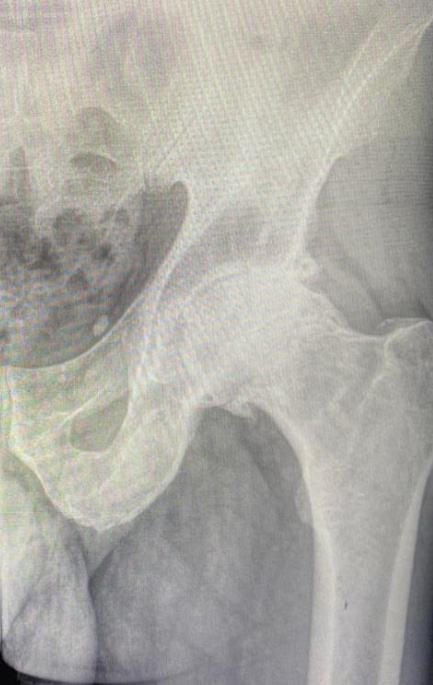

❗️Каковы же показания к операции?

Крайние стадии течения процесса разрушения суставного хряща (3,4ст.), в сочетании с стойким болевым синдромом, не поддающийся ЛФК и анальгетикам;

Переломы головки бедренной кости, сюда можно отнести 3 стадии течения асептического некроза;

Ложные суставы, образовавшиеся после предшествующих травм шейки бедренной кости;

Различные суставные деформации, в сочетании с разрушением суставного хряща, как при дисплазии впадины или бедренной кости.